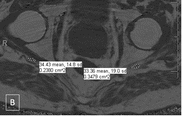

Zoomed images showing the fat fraction measurements. Zoomed image showing the sciatic nerves and their measurements at level A (figure A and B) and level B (figure C and D). (GIF 6 kb)